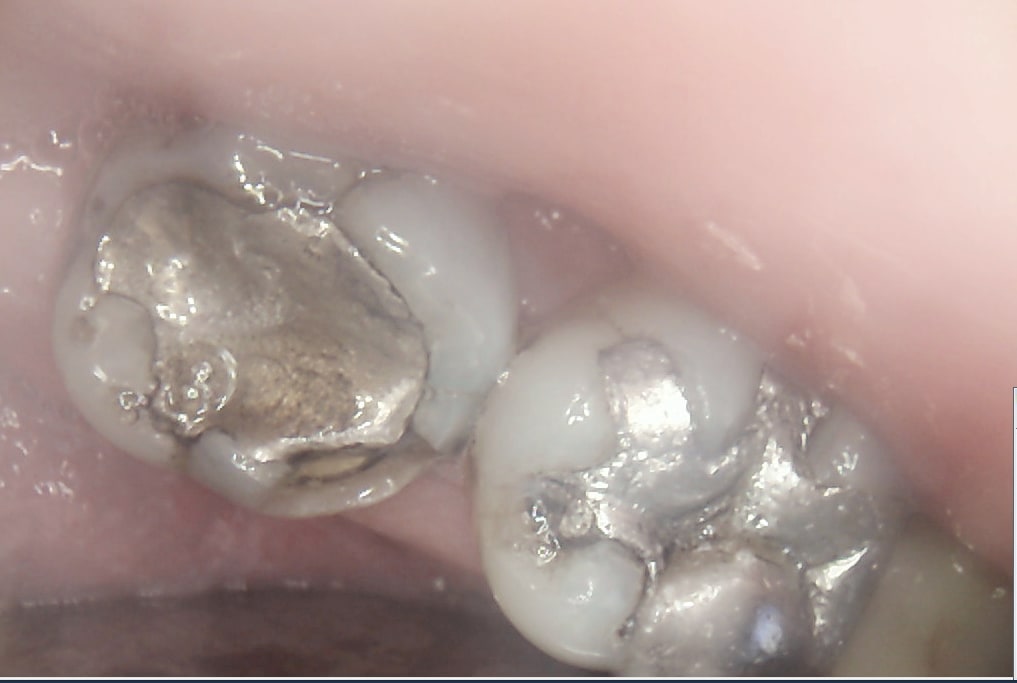

pit-être ! mais de là à m'y attaquer dès la 2ème séance alors que le gars il a gobé ses ATB en même temps que la dinde et le foie gras ... je sais pas ! ça me sctoche un peu ! et puis quand tu vois la 16 aussi ... Si quelqu'un a récupéré le patient de chicot , qu'il le lui rende SVP ! Ah oui un petit conseil de vieille branche , un AMG ça se sculpte , c'est pas pour rien qu'il y a des sillons sur une dent , ça sert pas seulement à faire joli ! ça permet aussi de répartir les forces , et d'éviter ainsi les fractures.

Mais bien sur avec des parois résiduelles de meme pas 1 mm. Ca n'est pas l'indication d'un amalgame.

Sinon je suis d'accord avec Chicot pour sa 37 : remettre un amalgame sur ça c'est risqué quand même. Un bon Overlay ou une couronne c'est plus l'indication

> Sinon je suis d'accord avec Chicot pour sa 37 : remettre un amalgame sur ça

> c'est risqué quand même. Un bon Overlay ou une couronne c'est plus l'indication

Ou une endo car l'état de la pulpe n'est pas au top après des années d'obturation volumineuse.